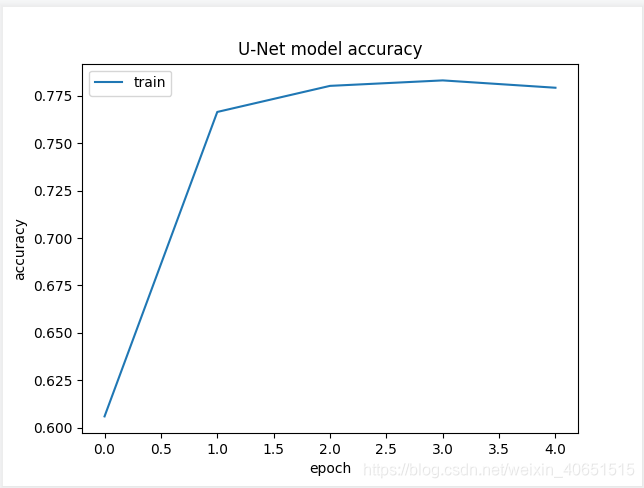

其实验结果的准确率曲线与模型训练次数的曲线如下所示:

从图中我们发现 U-Net模型在经过简化之后,其在细胞分割任务中已经达到了不错的训练效果结果,其准确率高达78%,为了进一步提高模型准确率,我们需要在模型设计环节设计完整的 U-Net模型,并加大模型的训练次数,这样就能使模型很轻松的达到95%左右。